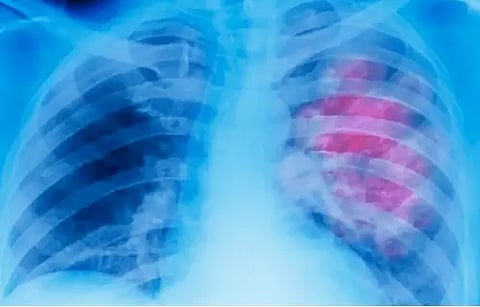

NEW DELHI: A newly developed artificial intelligence (AI) model could estimate one's age from their chest X-ray, new research published in The Lancet Healthy Longevity journal said.

The model can also signal chronic diseases such as hypertension and chronic obstructive pulmonary disease from the difference between estimated and chronological age, the research from Osaka Metropolitan University, Japan, said.

Chest X-rays could thus be useful as a biomarker of aging and longevity, they said, because they can show not only the shape of features within the body, but also details of internal organs and bones.